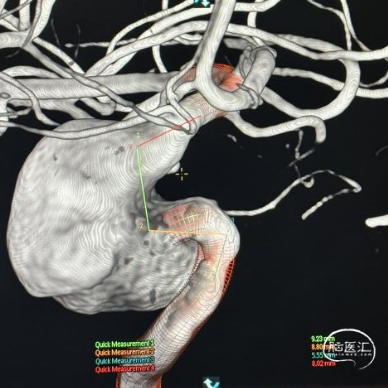

术前影像

脑动脉DSA提示右侧颈内动脉C5床突段动脉瘤。

右侧床突段载瘤动脉远端血管直径为1.8mm,载瘤动脉近端血管直径为5.2mm,瘤体宽13.1mm,瘤体最大宽度21.8mm。